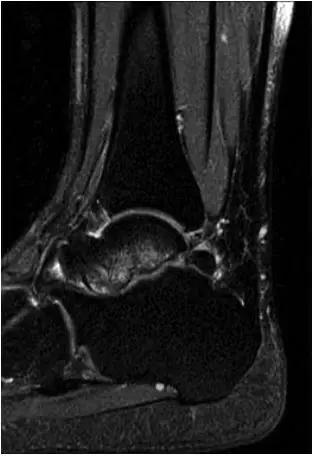

男,11岁,自述后踝下方疼痛,活动时为甚,并有一突起。

- MRI 检查示距后三角骨及周围软组织有水肿信号,距后三角骨和距骨之间正常的低信号纤维连接中断,出现液性信号。

3、MR表现:

- 三角籽骨或距骨后三角结构模糊和变形,T1WI信号降低, T2WI信号升高,

- 周围脂肪水肿,

- 踇趾长屈肌腱信号升高,见鞘膜积液,

- 胫骨后下跟骨上缘骨结构形态变化和信号异常,

- 三角籽骨和距骨退行性囊变。